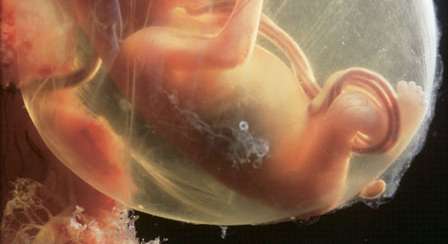

تهانينا! لقد قطعت شوطًا كبيرًا من الحمل من دون أن تُصابي بأي أذى إذ نسبة الإجهاض التلقائي في هذه المرحلة الآتية هي شبه مستحيلة. ولكن بالطبع عليك أن تأخذي الحيطة والحذر فلا يزال أمامك شوطٌ كبير لتصلي الى المرحلة النهائية من الحمل. يبلغ حجم جنينك حجم الليمونة أي 43 غرامًا وطوله 9 سنتيمترات. بدأ الوبر يغطّي جسمه الصغير. ستلاحظين انه اصبح يعبّر بوجهه كأن يعبس أو بالكاد يفتح عينه أو حتى أن يتبوّل ويمكن أن يمصّ إبهامه بفضل نبضات الدماغ. إنّ كليتيه تُنتج البول لتفرغها في السلوي. بالطبع أنتِ لا تشعرين بركلاته أو بتحرّكاته بعد في داخل جسمكِ ولكنّك تشعرين بطاقة كنتِ قد افتقدتِ إليها في المرحلة الأولى من الحمل. استفيدي من هذا الوقت للتخطيط واستغرقي في أحلام اليقظة فستشتاقين يومًا الى هذه الفترة.